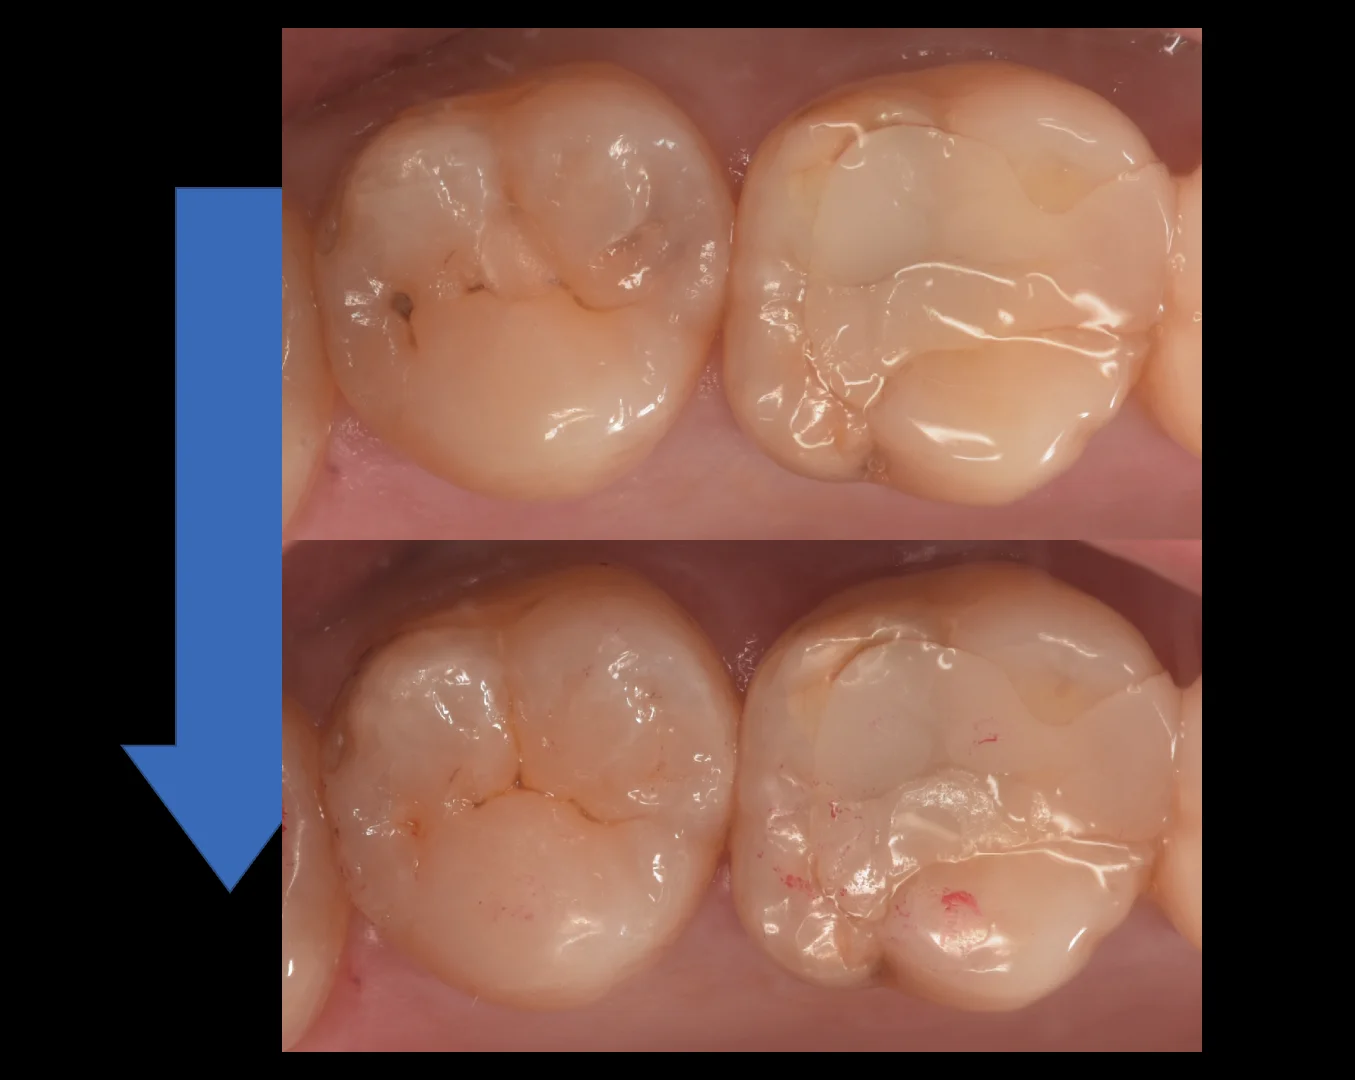

では症例写真に移ります。

まずは術前からです。

写真左側の歯を治療しました。

中心に小さく保険のCRを行なっており、手前の歯の間側・後ろの歯の間の小さな穴にそれぞれ虫歯があります。

そして詰め終わったのがこちらになります。

どうでしょうか?

違和感なくしっかりと詰め終われたかと思います。

個人的にはかなり良い仕上がりになったと思います。

1週間経って歯の色があってくると拡大視野を使用した歯科医師が診ても一瞬わからないんじゃないでしょうか?!

治療の術前術後がこちらになります。